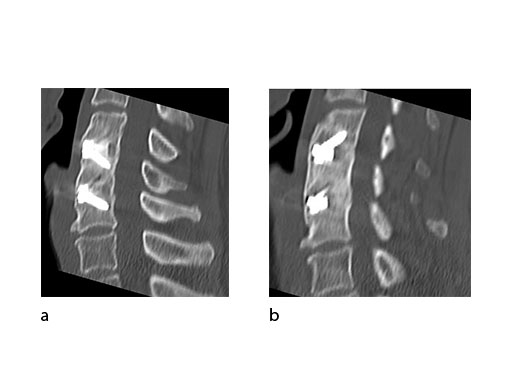

A 51-year-old woman was affected by cervical radiculo-myelopathy due to spinal and neuroforaminal stenosis. The preoperative CT scans are shown at Fig 4 and MRI at Fig 5.

The patient was treated by anterior cervical decompression and fusion (ACDF) with ZERO-P filled with ChronOS. No autologous bone graft was used. Postoperative images are shown (Fig 69).